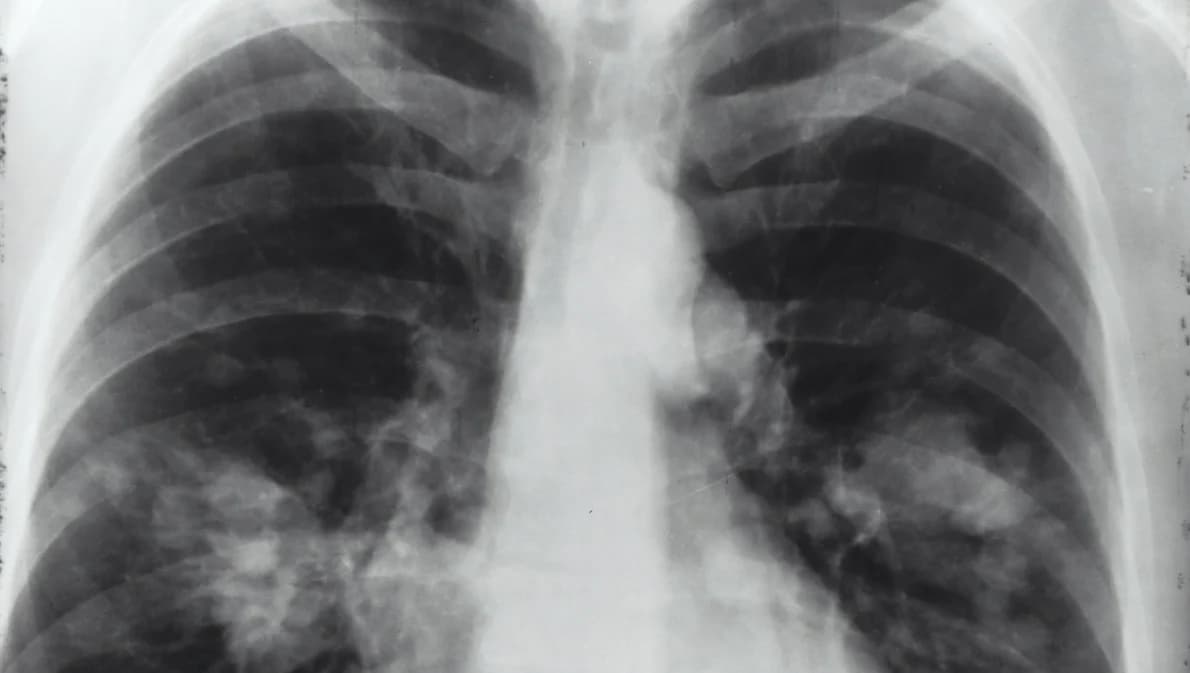

การวินิจฉัยโรคมะเร็งปอด ทำโดยการถ่ายภาพรังสีปอด (X-ray หรือ CT scan) ร่วมกับการตรวจหาเซลล์มะเร็งเช่นการตรวจจากเสมหะ หรือการตัดชิ้นเนื้อจากปอดมาตรวจ เมื่อพบว่าเป็นมะเร็งปอดแน่นอนแล้วแพทย์จะเป็นผู้ให้ข้อมูลเพื่อให้ผู้ป่วยและญาติร่วมตัดสินใจ โดยพิจารณาจากชนิดของมะเร็ง ระยะโรคและการลุกลาม ความแข็งแรงของผู้ป่วยเป็นหลัก สำหรับการรักษามีทั้งการผ่าตัด การใช้ยา การฉายแสง หรือรักษาร่วมกันหลายวิธี เนื่องจากมะเร็งปอดการตรวจคัดกรองให้พบโรคในระยะแรกทำได้ยาก และ มีอัตราตายสูง ดังนั้นการหลีกเลี่ยงปัจจัยเสี่ยงเช่นงดสูบบุหรี่ ป้องกันตัวจากการสัมผัสแร่ใยหิน หรือ มลภาวะ หลีกเลี่ยงอาหารไขมันสูง รับประทานผักผลไม้ให้มากขึ้น ออกกำลังกายสม่ำเสมอและพักผ่อนให้เพียงพอเพื่อเพิ่มภูมิคุ้มกันของร่างกาย และ รีบมาพบแพทย์เมื่อมีอาการผิดปกติจึงเป็นสิ่งสำคัญ